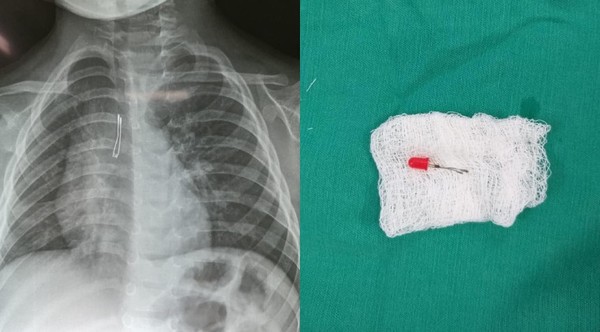

NIÑO DE 2 AÑOS INGIRIÓ FOQUITO DE SU JUGUETE Y DEBIÓ SER LLEVADO AL QUIRÓFANO

Un niño de tan solo 2 años tragó accidentalmente el foco de uno de sus juguetes, ocasionándole problemas respiratorios que derivaron en una intervención hospitalaria. Afortunadamente, el hecho no p… ...[Leer más]